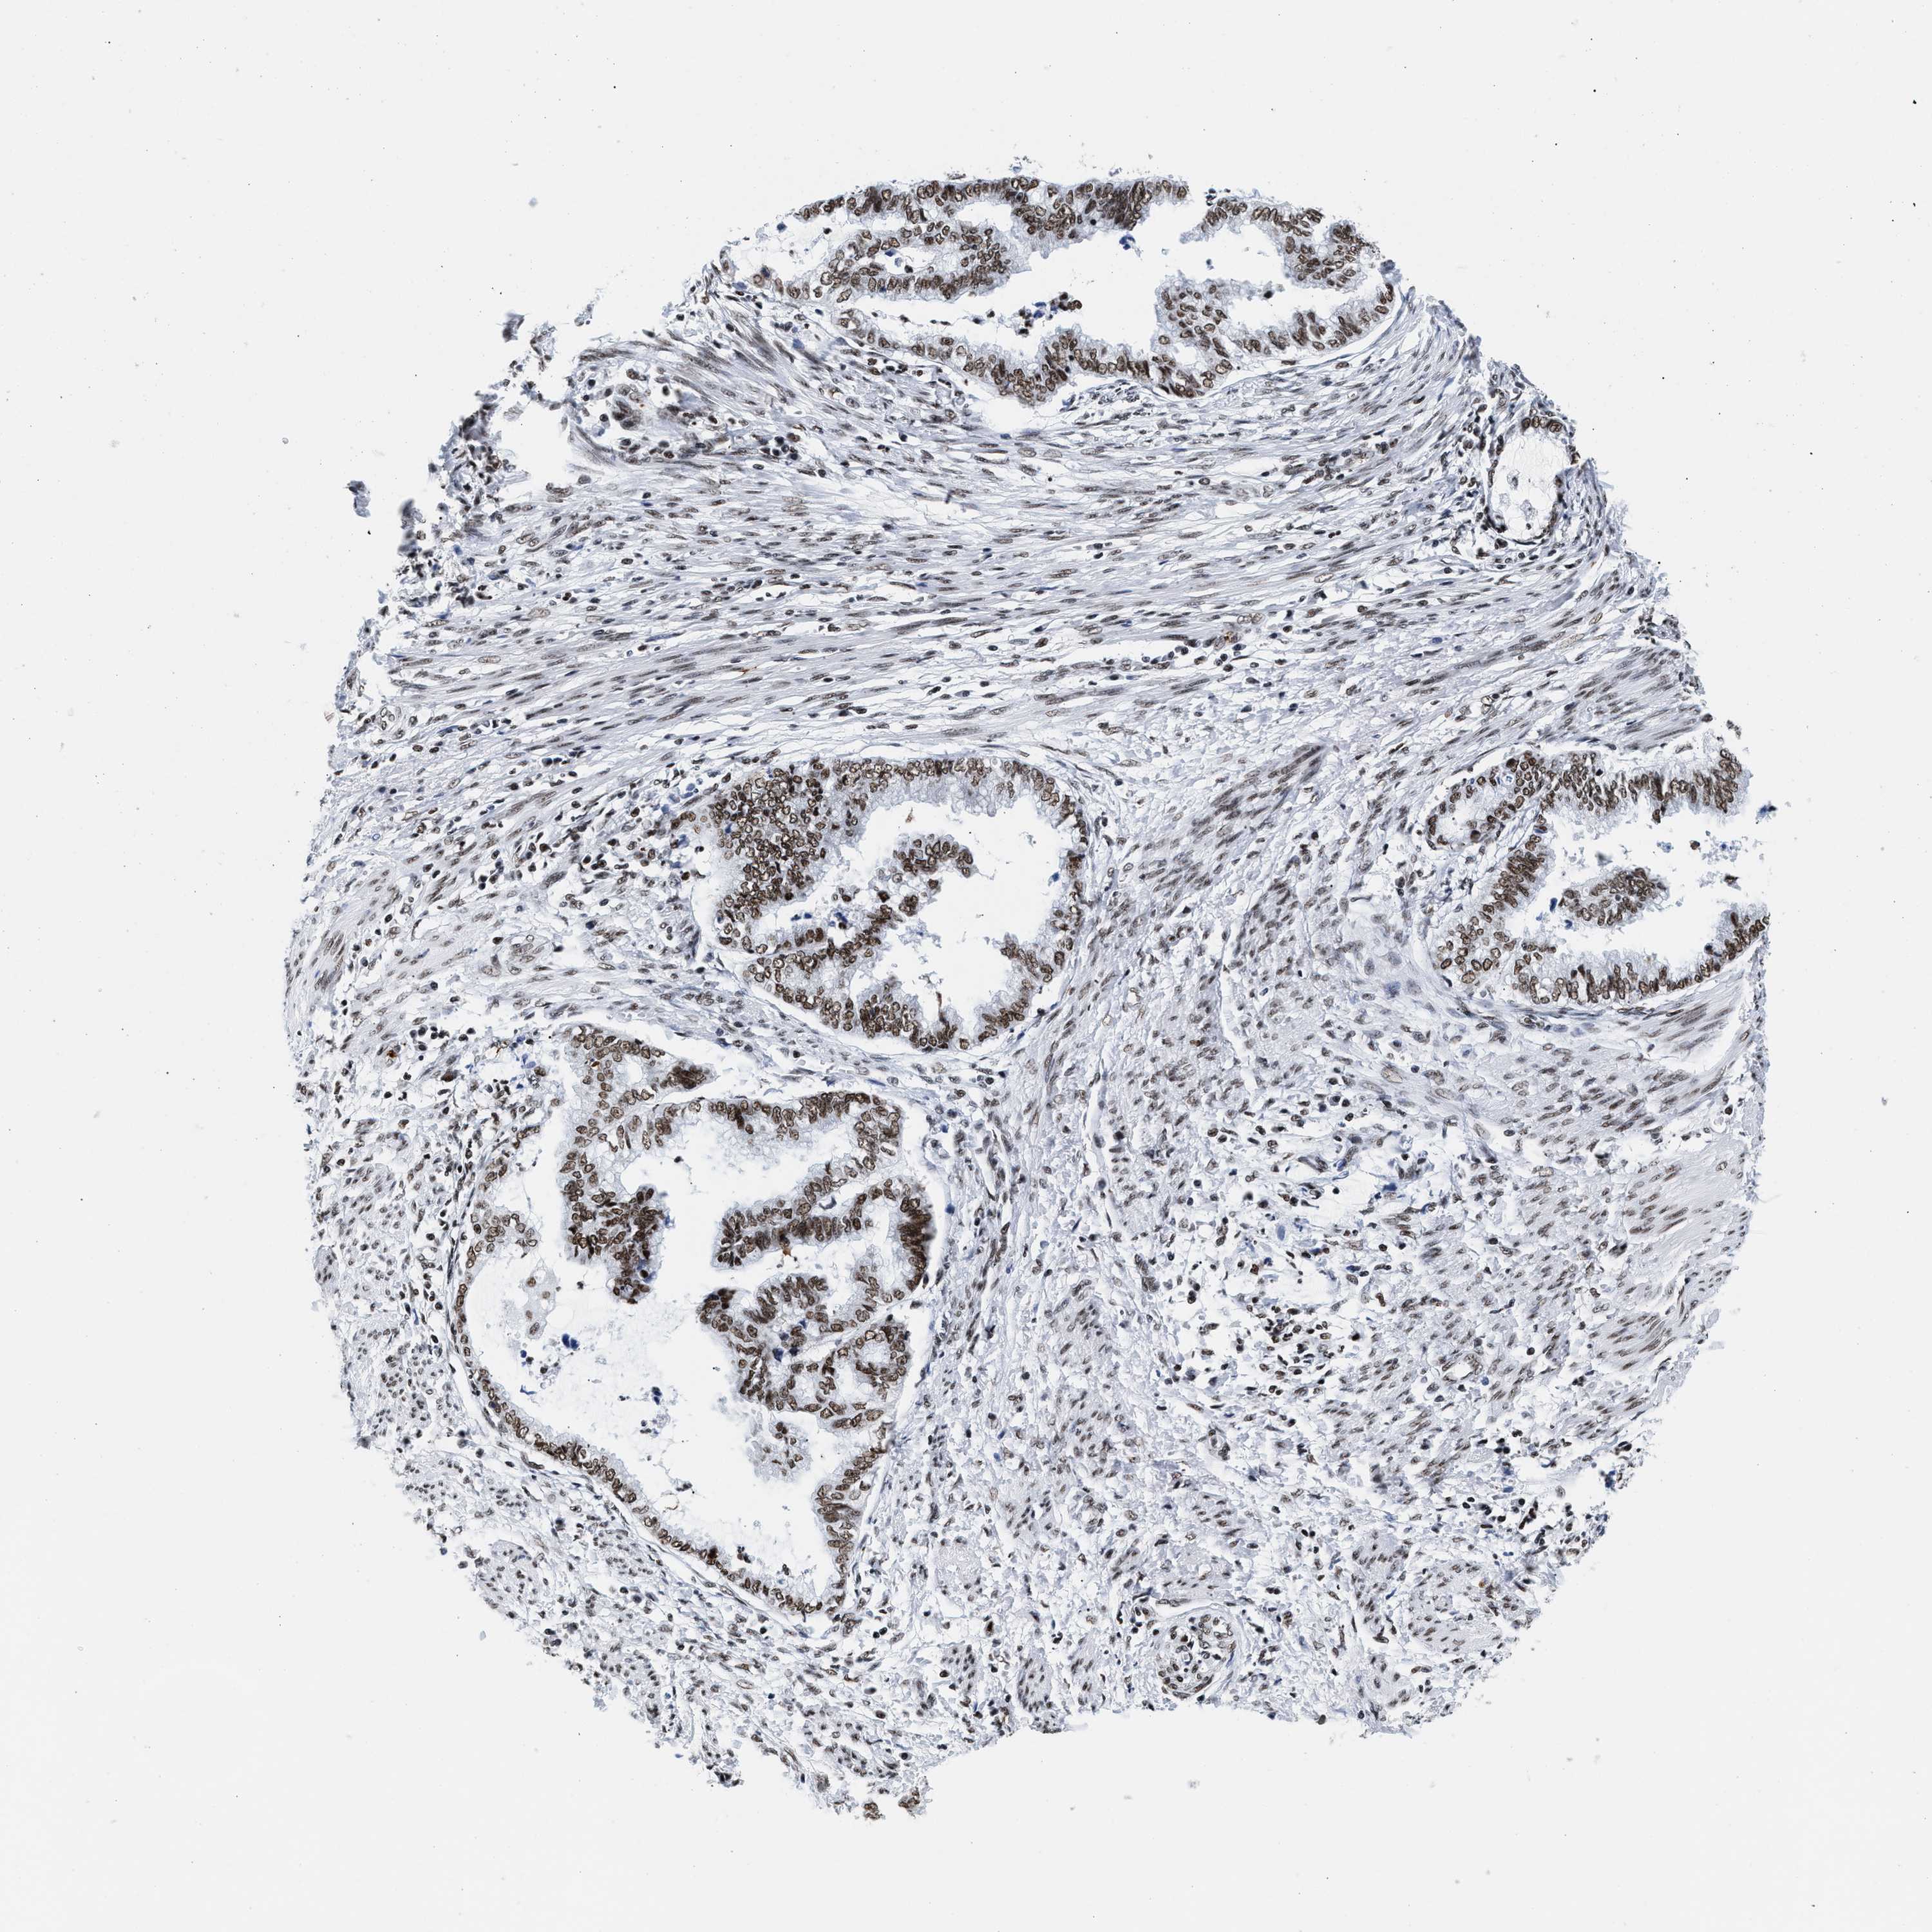

ENDOMETRIAL CANCER - Protein expressioni

A mouse-over function shows sample information and annotation data. Click on an image to view it in a full screen mode. Samples can be filtered based on level of antibody staining by selecting one or several of the following categories: high, medium, low and not detected. The assay and annotation is described here.

Note that samples used for immunohistochemistry by the Human Protein Atlas do not correspond to samples in the TCGA dataset.

Antibody stainingi

Antibody staining in the annotated cell types in the current human tissue is reported as not detected, low, medium, or high, based on conventional immunohistochemistry profiling in selected tissues. This score is based on the combination of the staining intensity and fraction of stained cells.

Each image is clickable and will lead to virtual microscopy that enables deeper exploration of all samples and also displays staining intensity scores, fraction scores and subcellular localization as well as patient and tissue information for each sample.

Antibody HPA020044

Antibody CAB022065

Staining

High

Medium

Low

Not detected

Intensity

Strong

Moderate

Weak

Negative

Quantity

>75%

75%-25%

<25%

None

Location

Nuclear

Cytoplasmic/membranous

Cytoplasmic/membranous,nuclear

Adenocarcinoma, NOS

Adenoma, NOS